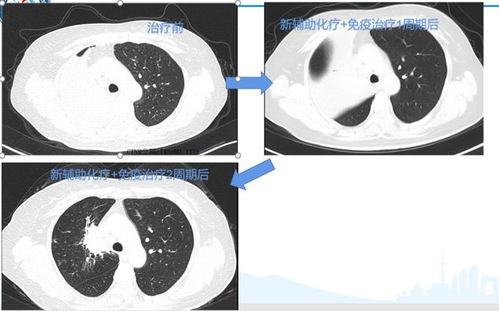

恶性肿瘤在短期内可呈现显著增长,特别是某些肺癌或乳腺癌,可能在短短数月内增长一倍。与之相反,良性肿瘤的生长速度相对稳定,甚至有可能停止生长。例如,皮肤纤维瘤多年可能无明显变化。

在诊断过程中,肿瘤体积大小并非唯一的判断标准。部分早期恶性肿瘤可能体积较小,如原位癌;而某些良性肿瘤,因位置特殊可能显得较大。在影像学特征上,恶性肿瘤通常表现为边界模糊、形状不规则,而良性肿瘤则多边界清晰、形态规则。